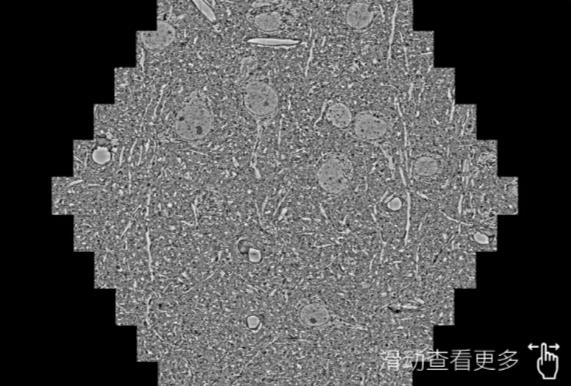

鼠脑切片。左图使用酉阳蔡司酉阳扫描电镜MultiSEM706对165μmx143pm面积区域成像,耗时仅需1.5秒。右图为鼠脑切片中30μm区域放大效果。样品由芝加哥大学B.Kasthuri提供。

使用蔡司高速酉阳扫描电镜MultiSEM对1mm²人脑皮层组织进行高分辨成像,并对其中的各种细胞结构进行三维重构分析。左图展示了2x3mm²组织平面中锥体神经元的三维重构效果。右图显示了局部体积神经元三维重构。图像由哈佛大学chtman实验室提供,渲染图由D. Berger 制作。